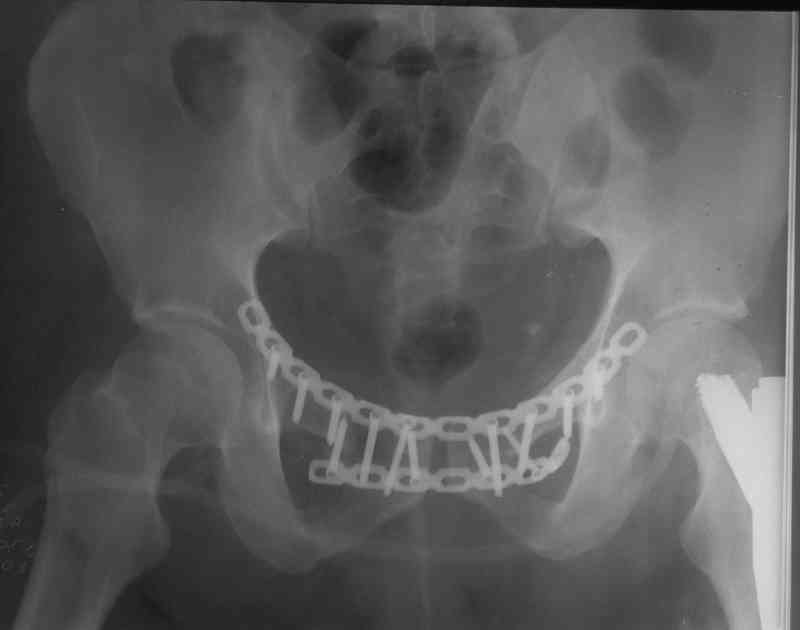

Вчера прооперировал больного.

Попытка низвести половину таза на тракционном столе ( скелетное вытяжение за бедро) безуспешная.

из переднего доступа добрался до правого КП сочленения , все запаяно костью, с помощью 2 шанцев винтов в крестец и подвздошную кость и элеватора репозиция, контроль ЭОП

и двумя пластинами фиксация.

Спереди, аппарат как рекомендовал Джолдас.

Снимки плохого качества( очень темные) завтра переделают и пришлю на конференцию.

На мой взгляд, смещение устранено и фиксация выглядит вполне анатомичной.

В приложении послеоперационные картинки.